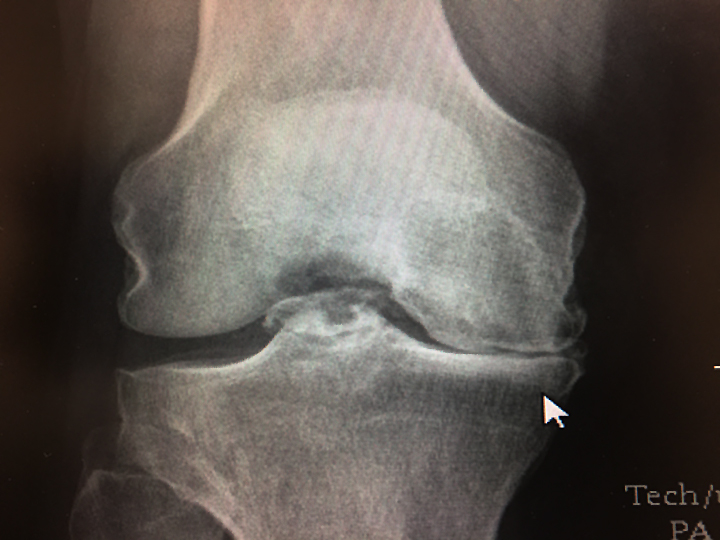

My left knee will give way to a man-made one on Thursday; we hope our readers will share even more news items and stories over the next few weeks! Life is ridiculously unfair. (Editor's Note: Warning - What follows is a long, whiny, "poor me" from the stereotypical whiny male who does not think he is nearly as stereotypically whiny as the typical male.) After years of limping around more and more slowly - 15 years after an orthopedic specialist told me I need a total knee replacement, but was too young - I have scheduled surgery. Most of my knee surgery medical kit is pictured here. Not pictured: The walker and PED hose that prevent post-operative blood clots. February is going to be a miserable month, wearing those ridiculous PED hose to prevent blood clots and learning (or so the surgeon says I must) to inject myself with 20 doses of a blood thinner known as enoxaparin sodium and slowly hobbling around on a walker as I re-learn to bend my left knee. It started in February of 1984, when I as a very non-athletic teenager, jumped up for a pass in basketball and when I came down my knee buckled. In four years time, I tore a hamstring, broke a foot, severed a tendon in my right thumb and had torn my ACL. I limped along the next 18 years more or less functioning normally although my knee progressively got a bit worse. Then in February of 2002 I was having a snowball fight with my sons, when my left leg totally froze up. I couldn't bend it for months, and even stepped aside to let the elderly ladies pass me going up the stairs. The x-rays and MRI showed my missing ACL, and cartilage that was mostly gone and bone chips in the middle of my knee where the "cap" should be. And on the left side of my knee, the bones would rub together since there was no cartilage. I limped along the next 15 years, wearing a tight brace with metal bands, and learning how much, and where I could walk. Because my job mostly involved office work, I managed to fair much better than someone whose job demanded physical labor. I even was able to usually play with the granddaughters and work outside. But over the past year or so, it has gotten worse. And after attending a couple of events at arenas with lost of steep steps in November, I was pretty much confined to limping around the house - or leaning on the grocery cart, surreptitiously using it as a walker. Late in December, I went to another surgeon, who told me I am almost - but not quite - too young. But after looking at the x-rays he said "What do you want?" So, today I am asking for your help. We will keep doing Vinton Today as before, although I will be doing all of it from the confines of my home office. I have a few stories I have been working on to share with you over the next few weeks, but I hope those of you who have so faithfully shared news items and photos will continue to do so, and that all of you who have news items to share but have never had the opportunity to share them with us, will do so. Oh, Mrs. C is offering to be helpful, although she scoffs at the idea of being instructed as my "caregiver," although not once after six childbirths, including c-sections, other surgeris and complications, did anyone tell me what I ought to do. It's true: Before I leave the hospital, they will make sure she knows how to properly care for me. And nope, nobody ever gave me such lessons when she went home! Life ain't fair, like that. And in other ways, too. I was heading to the lab a few days ago, pondering how to share with you all the details of my difficult journey ahead, when I saw an acquaintance who is about my age. I was about to unload on him my whole tale of woe, but first to be polite, I asked how he was. "We just found out I have cancer," he said, as his wife sat tearfully beside him. Like I said, life is ridiculously unfair. Sure, we need your help here at Vinton Today, and I hope you will pass on all of the stories you see, or experience. Contact us via email at vintontoday@hotmail.com, or on our Facebook page. But other people need your prayers much more than I do.